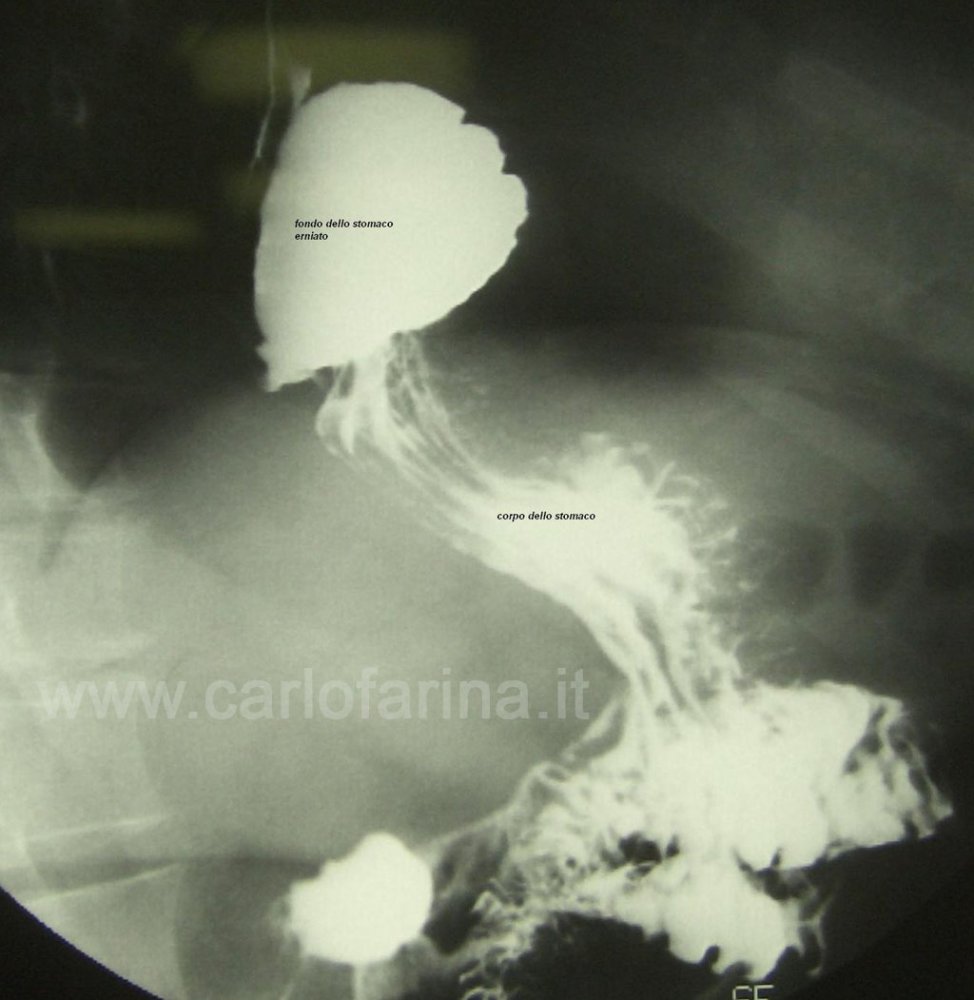

Per Ernia Iatale si intende lo spostamento di un tratto di stomaco al di fuori della cavità addominale attaverso il diaframma. Il diaframma e' quel muscolo a forma di tenda che separa il torace dall'addome. Attraverso il diaframma deve passare l'esofago attraverso un foro (Iato Diaframmatico)che a volte si allarga e consente allo stomaco di migrare nel torace Questa condizione patologica viene definita ERNIA IATALE.

Circa l'80 % dei pazienti con reflusso significativo ha anche un' ERNIA IATALE cioè un depiazzamento verso il torace della giunzione tra esofago e stomaco.

L'intervento ha lo scopo di riportare la porzione di stomaco erniata (l'ernia iatale) nella sua sede originale e di costruire una nuova valvola per impedire il reflusso.